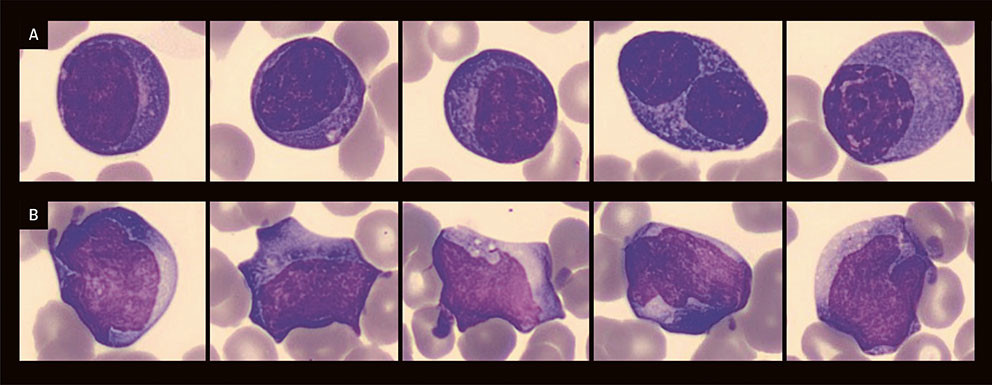

Blodutstryk ble laget på grunn av avvikende resultater ved maskinell analyse. Ved digital mikroskopi av perifert blodutstryk ble det ikke observert schistocytter, men 6,3 % plasmacelleliknende celler og atypiske lymfocytter (figur 1), i tillegg til svært mange ødelagte celler (kjerneskygger), som utgjorde 58 % av leukocyttene. Bildet ble av laboratorielege vurdert å kunne passe med virussykdom, som denguefeber. Et nytt blodutstryk, laget med skånsom sentrifugeringsmetode, viste at de ødelagte cellene i stor grad bestod av plasmacelleliknende celler, som nå utgjorde 33 % av leukocyttene. Mikrobiologisk avdeling kunne dagen etter innleggelsen melde om positiv denguevirustest (IgG, IgM og virusantigen NS1). Ved gjentatt undersøkelse av pasienten ble det avdekket petekkier på ekstremitetene og større ekkymoser som følge av trykk fra blodtrykksmansjett og etter blodprøvetaking (figur 2). Albuminverdien i serum hadde falt til 16 g/L. Intravenøs og oral væskebehandling ble videreført.

Atypiske lymfocytter er reaktive lymfocytter som kan ses ved virussykdommer, slik som mononukleose. Cellene er store, med rikelig blått cytoplasma (som uttrykk for aktiv DNA-syntese), og ligner en mellomting mellom lymfocytter og monocytter (figur 1b). En markant økning i antall plasmaceller er imidlertid sjeldnere. Plasmacytose er et vanlig funn i blodutstryk ved denguefeber (14). I en prospektiv studie ble polyklonale plasmaceller påvist hos 73 % av pasientene med denguefeber i løpet av første sykdomsuke (15), og i visse tilfeller kan plasmacytosen være så uttalt at plasmacelleleukemi må vurderes som differensialdiagnose (16). Behandling av denguefeber er symptomatisk, og spesifikk antiviral terapi er ikke kjent. Verdens helseorganisasjon (WHO) anbefaler innleggelse i sykehus ved varselmanifestasjoner (5, 6). Væskebehandling er sentralt, mens blodplatetransfusjon ikke anbefales med mindre det foreligger blødninger og alvorlig trombocytopeni (< 20 × 109/L). Det er ikke anbefalt å gi steroidbehandling ved dengue sjokksyndrom, og det finnes ingen evidens for at IVIg-behandling bedrer prognosen ved alvorlig dengue.